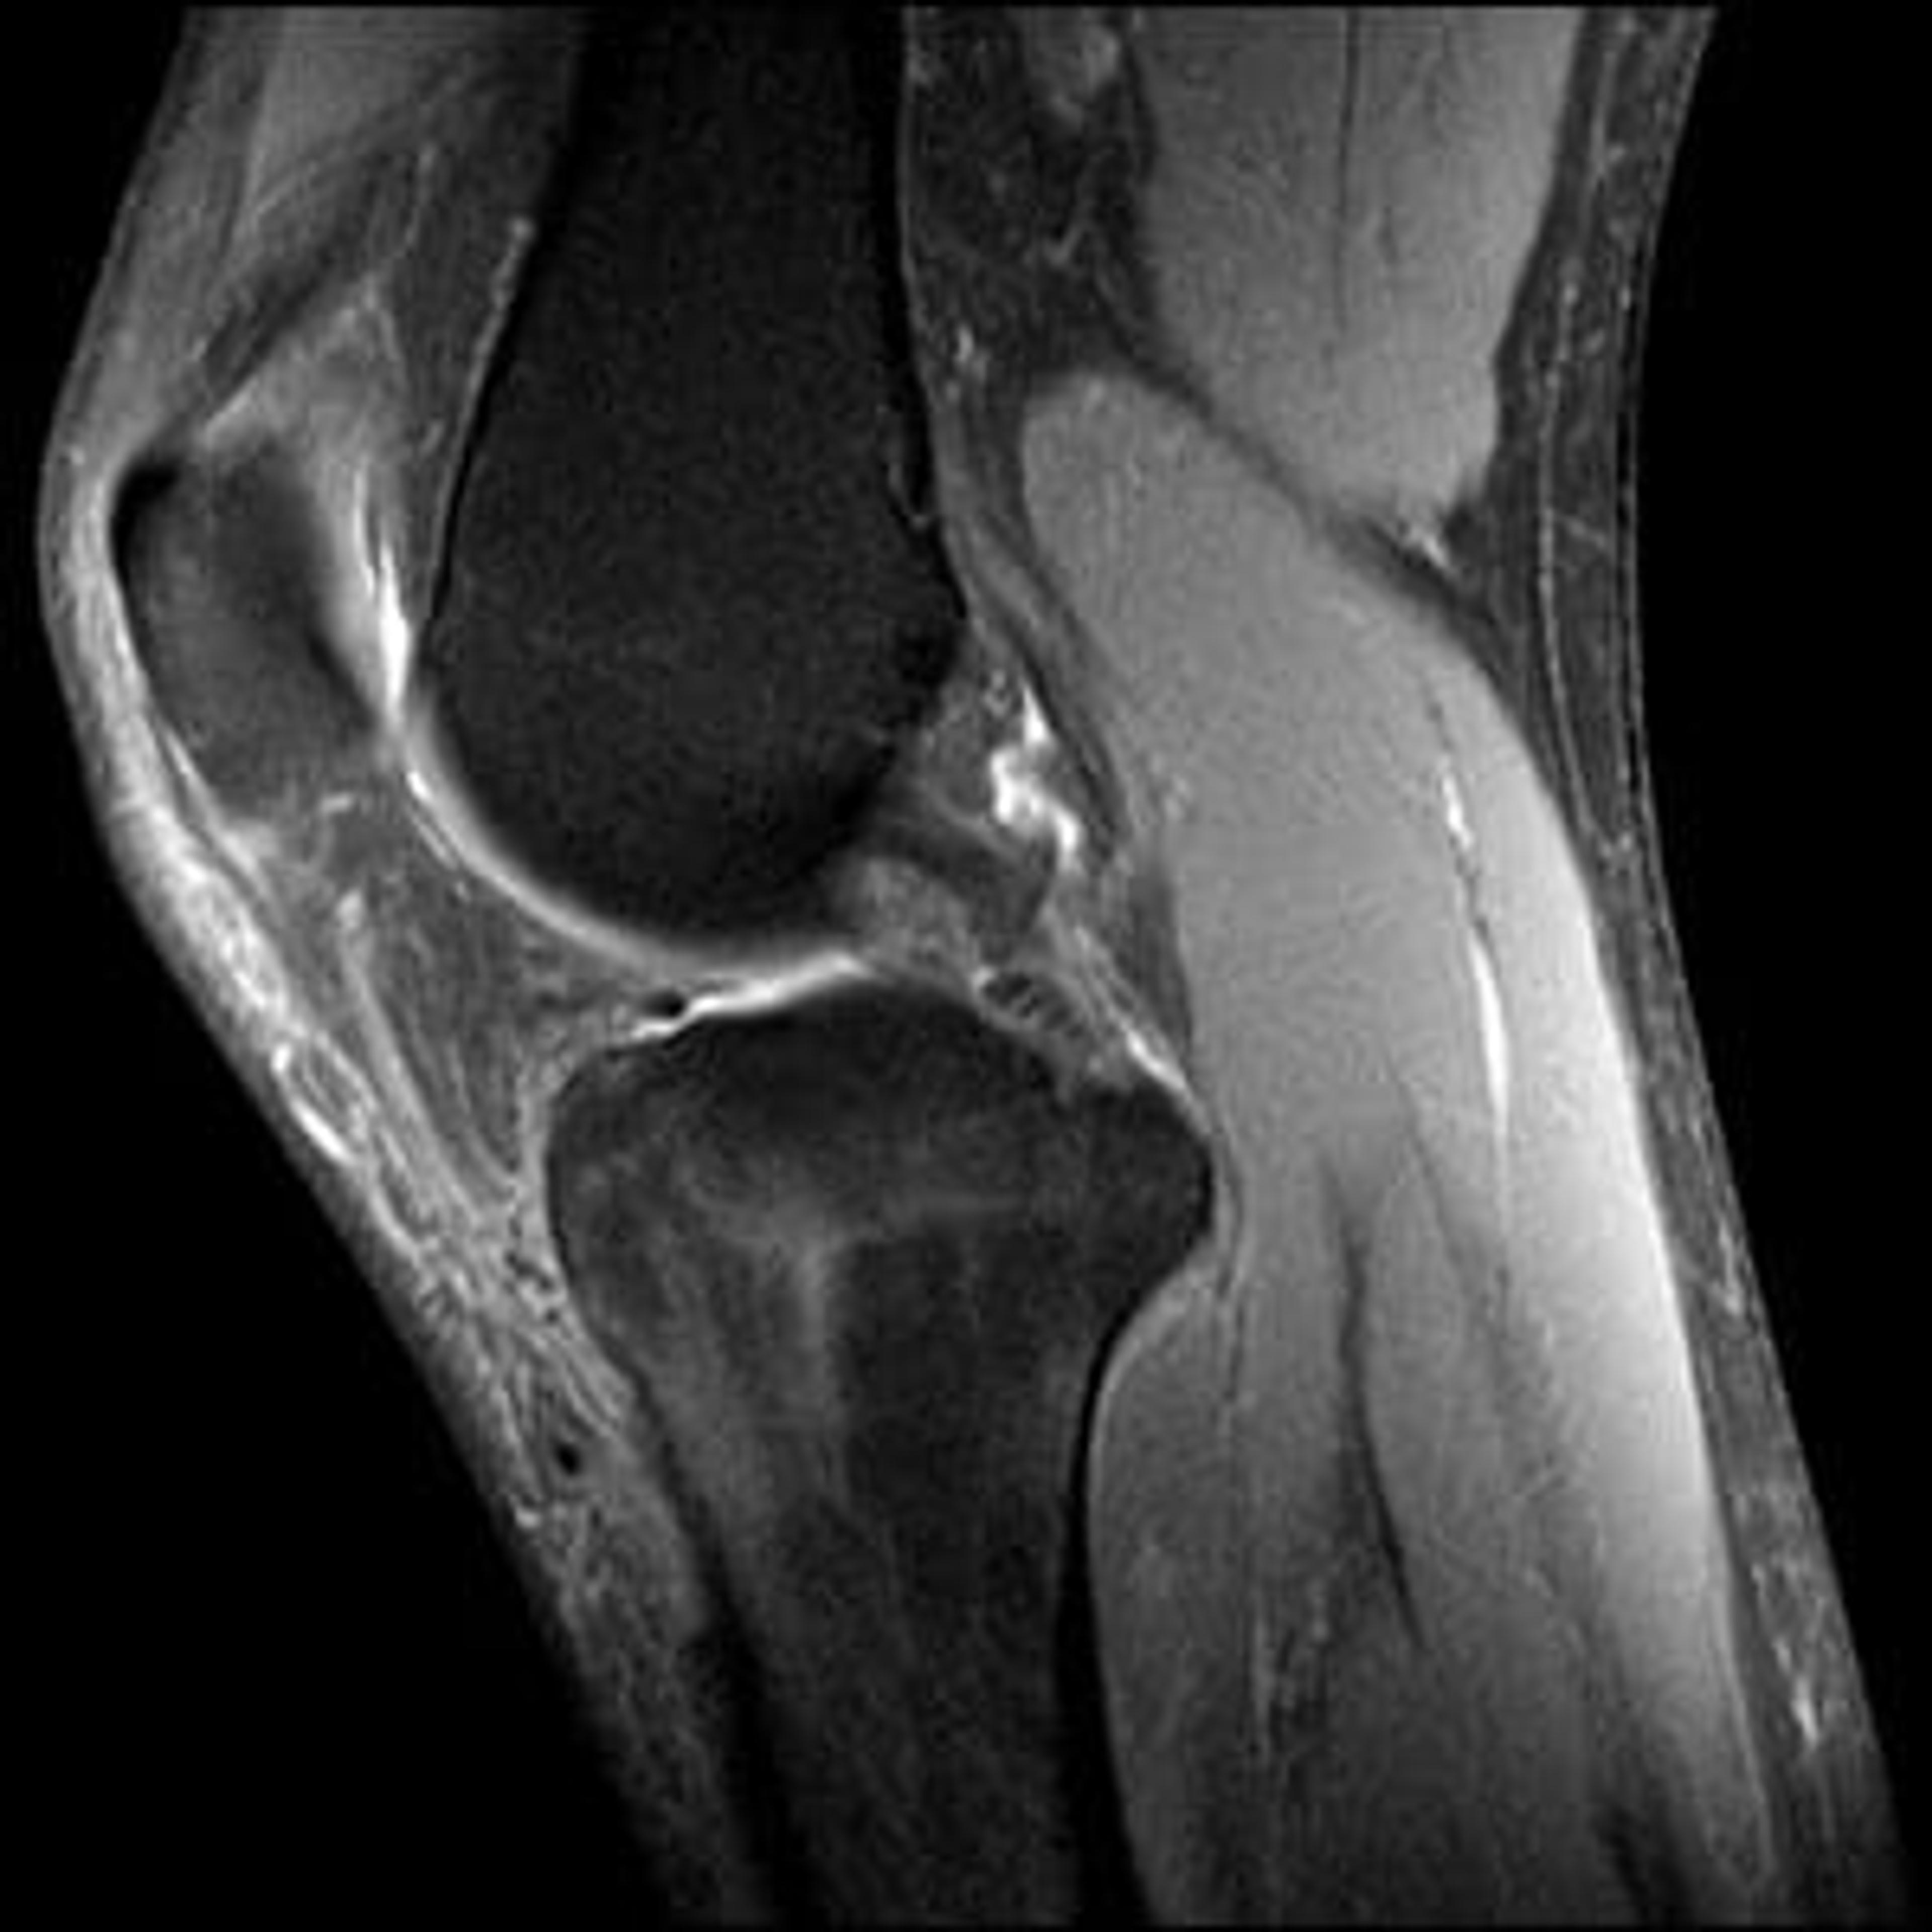

I’m told this really isn’t good, a bone edema is indicated.

MRIs and a few appointments with my orthopedist and physician assistant produced new diagnoses that were relatively good news: a serious bone marrow edema at the top of my left tibia or “shin” bone; a very minor, “sub-clinical” fracture along with the bone edema; and a tendon peeling off a bit from the same bone on the inside of my leg. Bone marrow edema, also known as a “bone bruise,” is a swelling of a bone, filling it with fluid, such as blood and water, something just shy of a bone break when it is caused by an acute incident. The surgeon couldn’t quite say that my encounter with the wilderness caused my injury as some of it was indicative of stress and some of it was indicative of a specific accident. The result is the same. I have a minor, but serious injury.

All of this is relatively good news. It isn’t anything wrong with my cartilage or ligaments. Surgery is not projected to be in my future. It is less traumatic than an actual, “real” fracture.